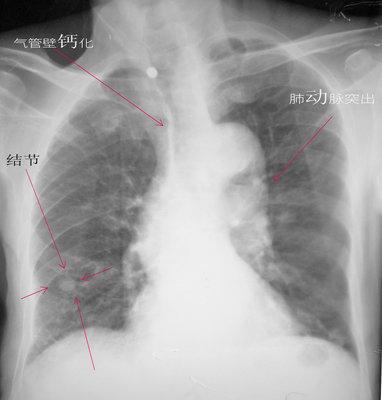

肺上有结节5个细节揭示有没有癌细胞医生教你看ct片

一起来看片~5分钟找到"肺部小结节"

肺结节ct图片

肺结核片子

肺癌片子图